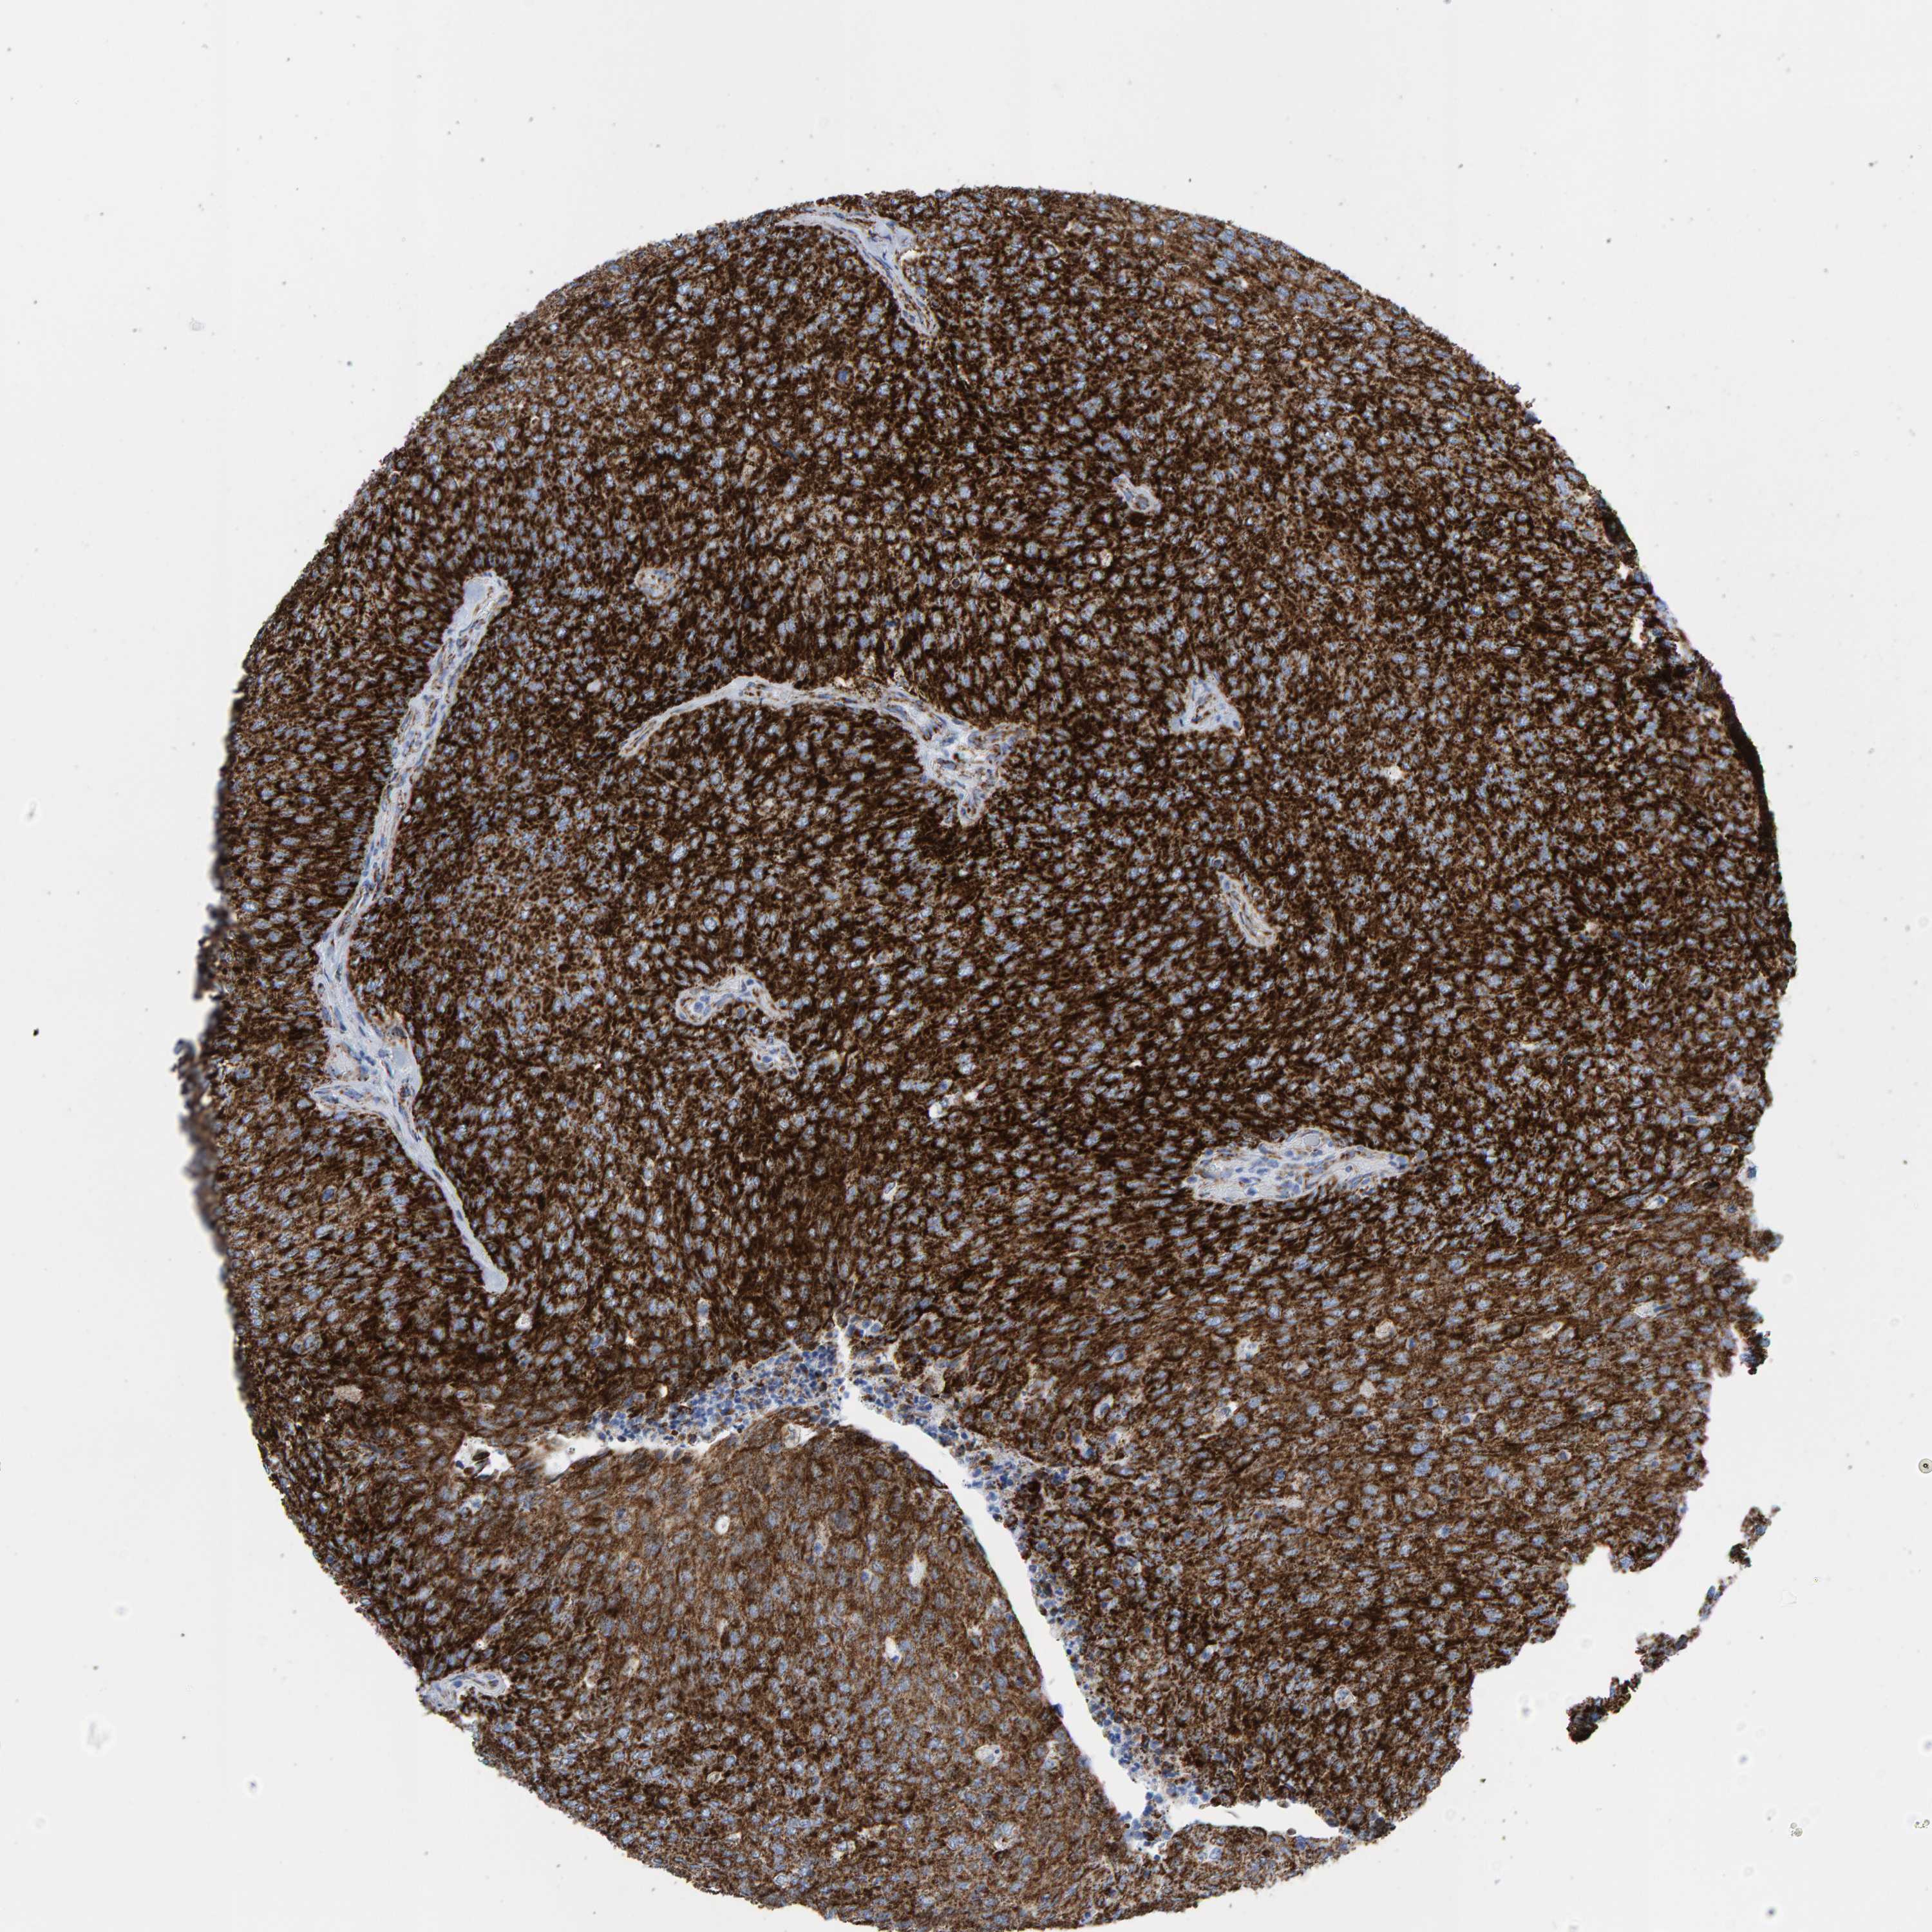

UROTHELIAL CANCER - Protein expressioni

A mouse-over function shows sample information and annotation data. Click on an image to view it in a full screen mode. Samples can be filtered based on level of antibody staining by selecting one or several of the following categories: high, medium, low and not detected. The assay and annotation is described here.

Note that samples used for immunohistochemistry by the Human Protein Atlas do not correspond to samples in the TCGA dataset.

Antibody stainingi

Antibody staining in the annotated cell types in the current human tissue is reported as not detected, low, medium, or high, based on conventional immunohistochemistry profiling in selected tissues. This score is based on the combination of the staining intensity and fraction of stained cells.

Each image is clickable and will lead to virtual microscopy that enables deeper exploration of all samples and also displays staining intensity scores, fraction scores and subcellular localization as well as patient and tissue information for each sample.

Antibody HPA022853

Antibody HPA023043

Antibody HPA023048

Staining

High

Medium

Low

Not detected

Intensity

Strong

Moderate

Weak

Negative

Quantity

>75%

75%-25%

<25%

None

Location

Nuclear

Cytoplasmic/membranous

Cytoplasmic/membranous,nuclear

Urothelial carcinoma, Low grade

Urothelial carcinoma, High grade